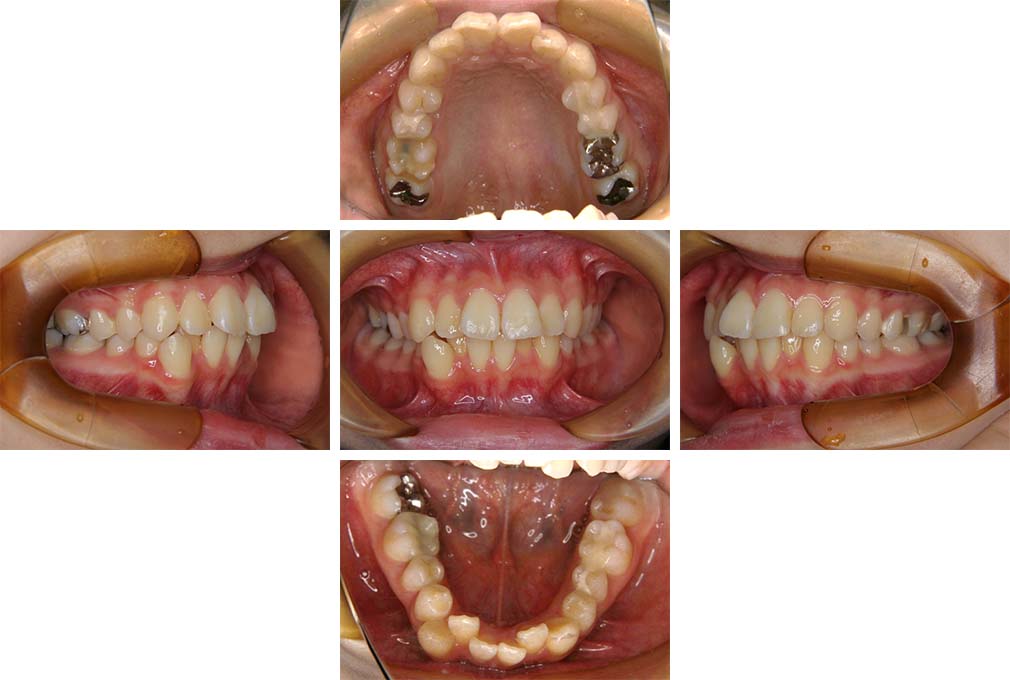

CASE:01

叢生を伴う骨格性上顎前突

初診時年齢 15歳10カ月

性別 男性

治療費の目安 約75万円程度(治療開始時)

上顎前歯の前突と叢生を主訴として来院された。大臼歯関係は左右側ともにⅡ級で上顎の方が前方に位置していた。叢生を伴う骨格性上顎前突と診断し、上下顎小臼歯抜歯を行っていただきマルチブラケット装置に顎外固定装置を併用して動的治療を行った。顎外固定装置や矯正用ゴムの使用など協力状態も良好で、動的治療期間2年0カ月、調整来院20回でマルチブラケット装置を撤去し保定へ移行した。動的治療終了後10年0カ月を経過したが保定移行時とほぼ同様の咬合状態で良好な状態を保っていた。

治療前

15歳10か月

治療後

動的治療期間2年0カ月

18歳5か月

10年経過

動的治療終了後10年0カ月

28歳5か月